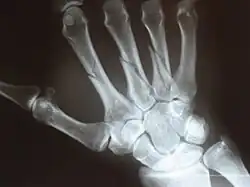

X-ray

Fracture

The neck of a metacarpal is a common location for a boxer's fracture, but all parts of the metacarpal bone (including head, body and base) are susceptible to fracture. During their lifetime, 2.5% of individuals will experience at least one metacarpal fracture. Bennett's fracture (base of the thumb) is the most common.[4] Several types of treatment exist ranging from non-operative techniques, with or without immobilization, to operative techniques using closed or open reduction and internal fixation (ORIF). Generally, most fractures showing little or no displacement can be treated successfully without surgery.[5] Intraarticular fracture-dislocations of the metacarpal head or base may require surgical fixation, as fragment displacement affecting the joint surface is rarely tolerated well.[5]

X-ray image of right hand with thumb on left. -

Multiple fractures of the metacarpals (aka broken hand). (Right hand shown with thumb on left.) -